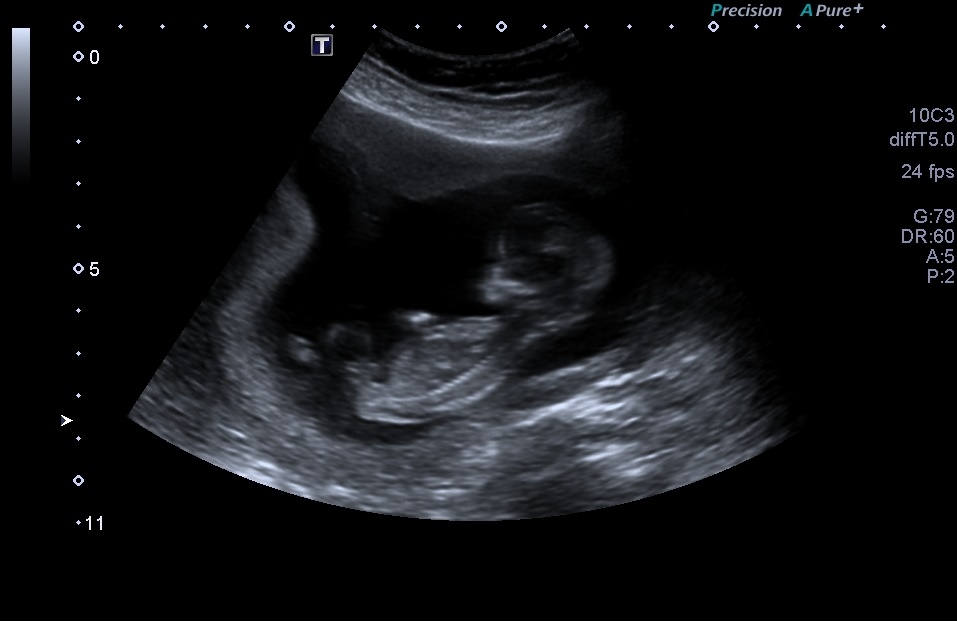

Attachment 20622Attachment 20621 Attachment 20623 Attachment 20624

I hope you can make a guess, i have to wait another 6-7 wks to find out the gender and i just like to hear your guesses

I'm gonna say boy too.the nub in your last pic is very boyish x